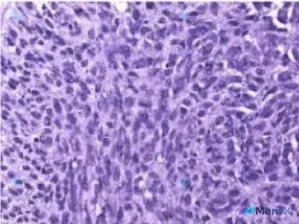

整理了一个很有启发的病理读片思路,这个病例的形态学组合挺容易踩坑的,分享给大家。 先看病例核心形态学表现 - 背景:淋巴组织结构破坏 - 肿瘤细胞:弥漫性增生的异型肿瘤细胞,体积大,多形性明显 - 细胞形态:梭形 + 多边形混合,部分可见多核巨细胞 - 核特征:核大深染,核内不规则假包涵体,多个核仁...

在论坛上看到一张很有讨论价值的HE染色病理切片,整理了一下自己的分析思路,和大家分享。 先看一下切片里的关键形态学表现 1. 整体结构 - 正常的分层结构完全消失,取而代之的是大片增生的细胞 - 细胞排列紧密、拥挤,呈片状/弥漫性生长,缺乏正常连接 - 局部可见坏死、脱落及少量炎细胞浸润 2. 细胞...